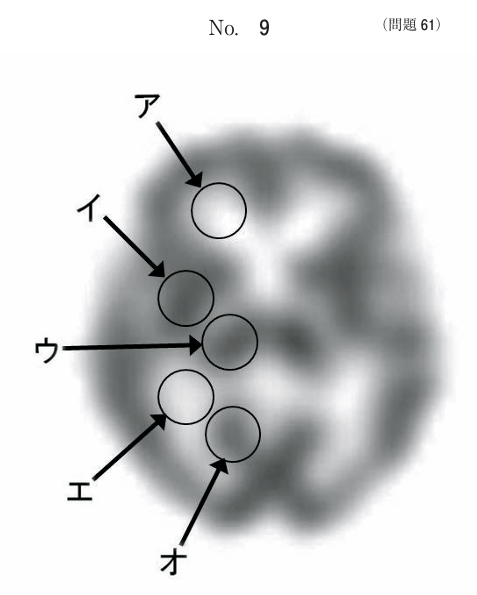

午前/問題61

脳血流 SPECT 軸位断像(別冊No. 9)を別に示す。視床はどれか。

1.ア

2.イ

3.ウ

4.エ

5.オ